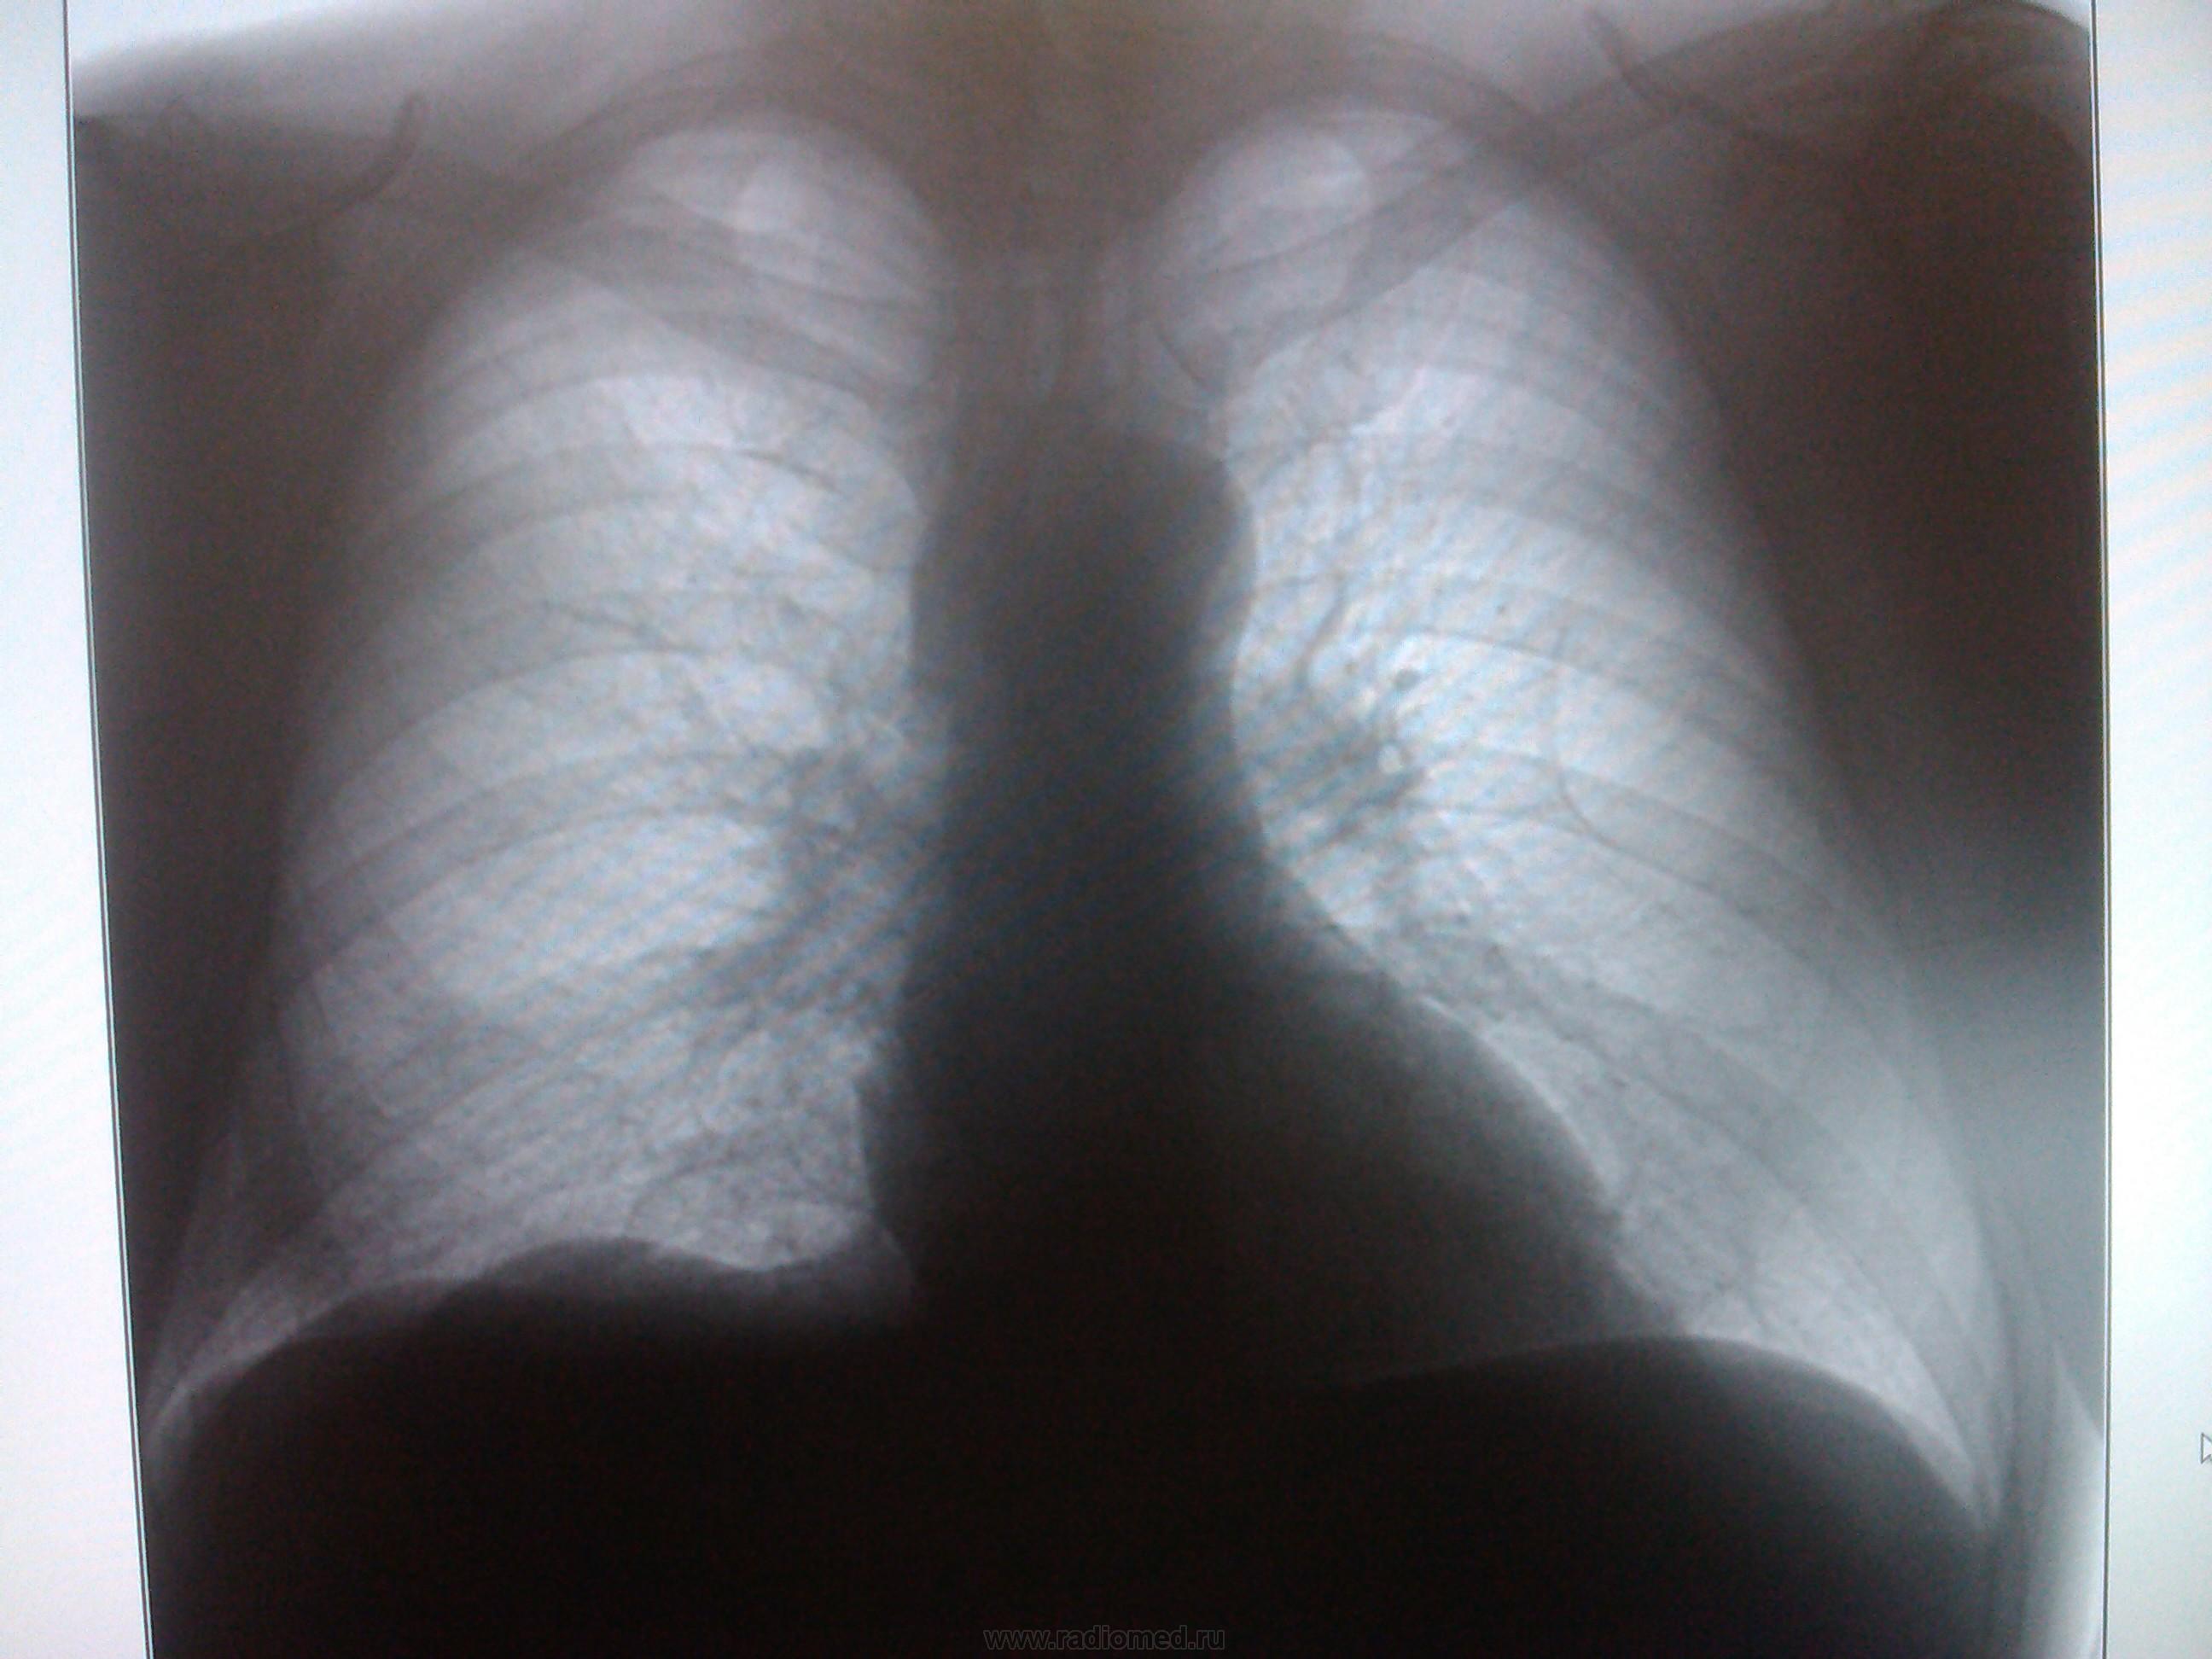

май 2014 г.

Сначала ветку целиком не открыла, думала вопрос касается только первого снимка, высмотрела подозрительную тень на уровне 5 ребра, и правый корень не понравился. С учетом продолжения однозначно периферический

Пермферический рак нижней доли правого легкого в S9-10(учитывая отрицательную динамику за год)

Согласна с коллегами. Справа в S 10 периферическое образование, учитывая рост, более вероятно  C-r.  Cлева в среднем поле   воздушная киста

периферический рак справа + кисты в левом легком  в средних и нижних отделах

Господи! Какой ретроспективный анализ? Она-оно (зло) растет себе и растет, кстати, на фоне этих кист в обоих легких ( Nobody, Вам-особенный респект!)